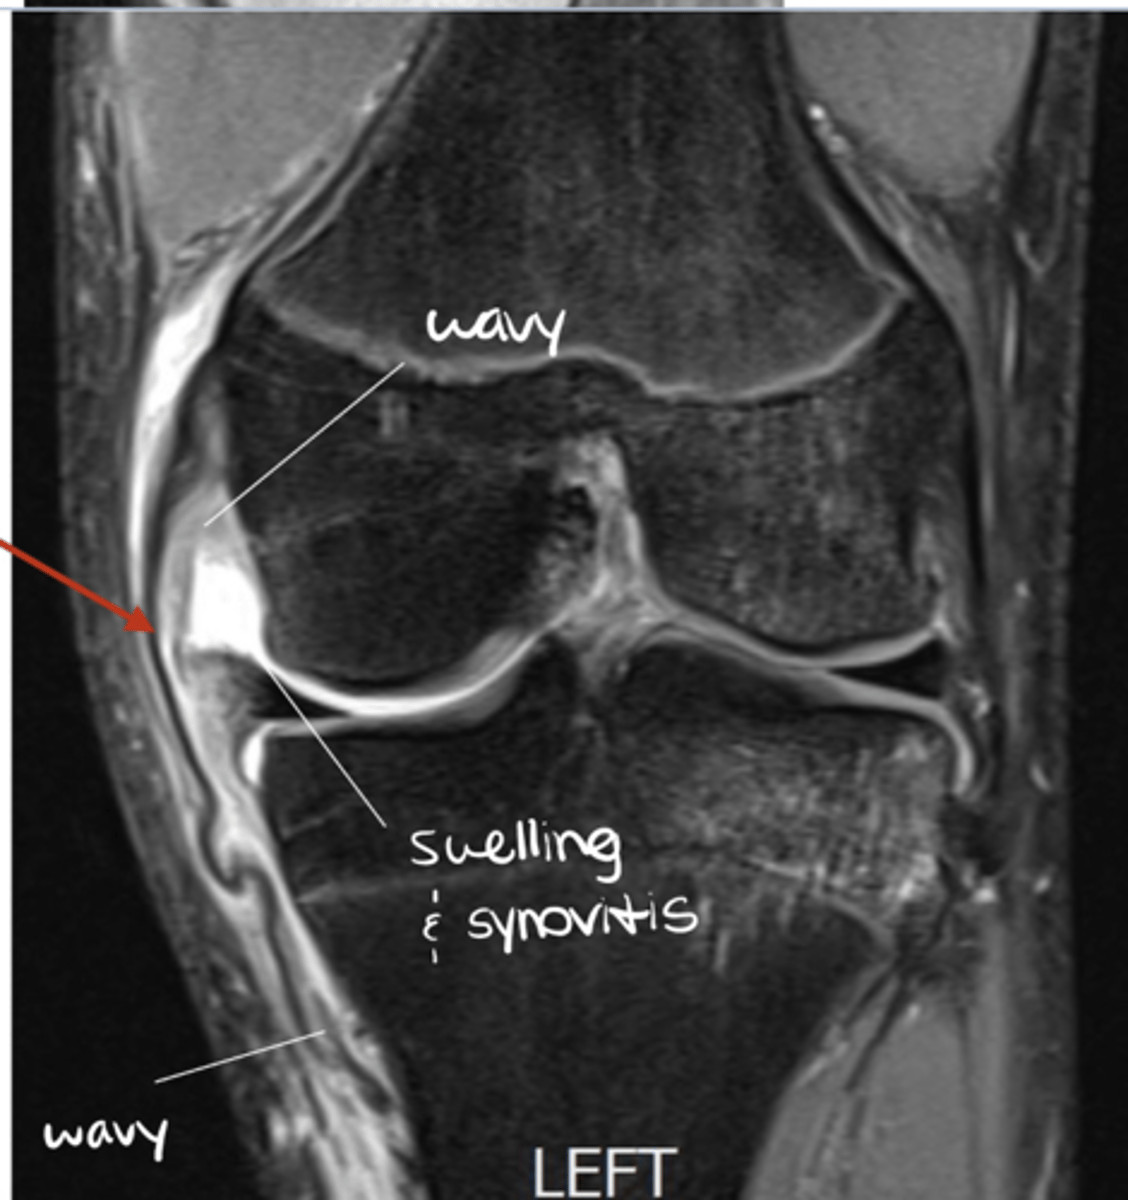

Grade III MCL tear

Define the pathology.